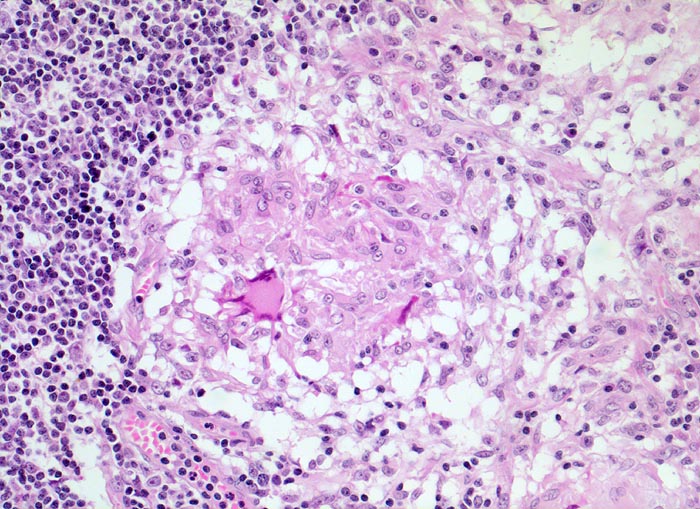

In der mittleren Dermis bilden sich Nekroseareale, welche von palisadierenden Histiozyten, mehrkernigen Riesenzellen und eosinophilen Granulozyten demarkiert werden. Die regionären Lymphknoten zeigen ebenfalls eine retikulozytär abszedierende Entzündung. Diese ist jedoch nicht spezifisch. Sie kommt auch vor bei Yersiniose, atypischer Mykobakteriose, Sporotrichose, Tularämie, Tumoren, Lymphogranuloma venereum und Coccidiomykose.